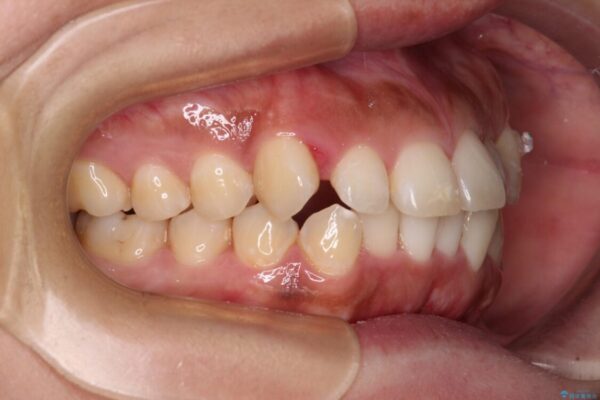

前歯の叢生と八重歯を気にして来院された患者様です。

治療前

• 【モニター】カリエール・ディスタライザーを併用した八重歯のインビザライン矯正 治療前画像